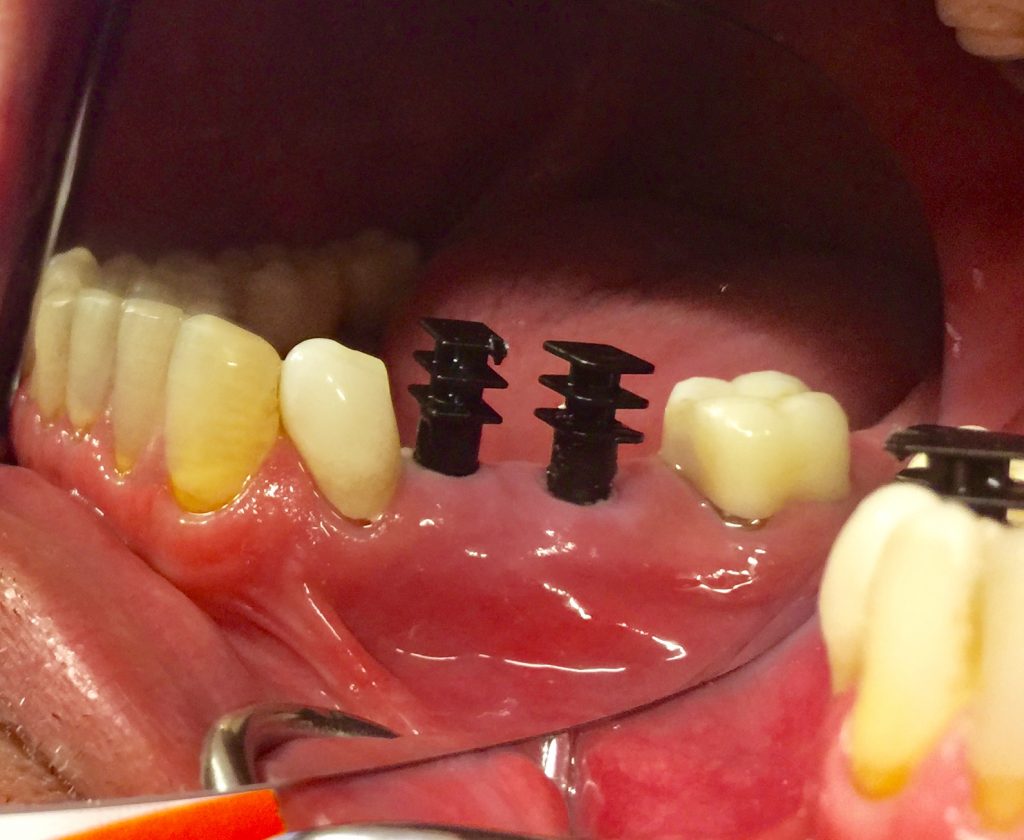

Autores: PRÓLOGO Asimismo, desde el punto de vista pedagógico, el profesional nobel en la materia tiene a su alcance la posibilidad de corregir cualquier posición implantaría en el ordenador, planear los provisionales y plasmarlos en la bio réplica antes de tocar al paciente a operar. Todos estos razonamientos nos llevan a presentar un caso de condiciones muy favorables para poner en práctica estos métodos como primer acercamiento a una Odontología Digital de alta calidad, con medios informáticos, que ya están presentes en la profesión de hoy en día, y será la protagonista única del futuro. Por otro lado, después de numerosos estudios que nos llevan a plantear el “gap” entre implante y pilar(abuttment), como principal responsable de la periimplantitis dado que la microbiota presente en el mismo es imposible de limpiar y en su presencia la cortical ósea reacciona reabsorbiéndose, nos ha llevado a utilizar implantes monobloc ya que los ejes implantarios y protéticos coincidían, y nos permitían su uso. Además, el circonio, ha mostrado a la luz de estudios muy recientes, una preservación y adhesión de los tejidos blandos superiores al titanio, tanto en su tratamiento de superficie de la rosca como a nivel gingival. DESARROLLO Paciente varón de 68 años, con antecedentes de radio/quimioterapia cinco años antes, con Rehabilitación Oral de los cuatro cuadrantes, con una Oclusión Mutuamente Compartida conservada, (REF.8) la que fracasa en el cuadrante 4, 19 años después. El mismo presentaba un puente de porcelana sobre circonio con pilares en 44 y 47, reemplazando el edentulismo de 45 y 46. Se produce la fractura del PM del 44, y ante una endodoncia antigua y corta, se decide implantar las zonas edéntulas, conservando temporariamente los pilares, hasta producida la oseointegración, para entonces también exodonciar el 44. DIAGNÓSTICO Tomamos impresiones del maxilar antagonista, Arco Facial Estático y realizamos montaje del mismo mediante la sistemática ARTEX. Producimos la relajación del músculo Pterigoideo Externo, para obtener la ORC (Oclusión en Relación Céntrica) mediante el método de Laminillas de Long, basado en el concepto de INERVACIÓN RECÍPROCA. Esto nos permitirá montar el maxilar inferior, tanto en su forma de: La primera para practicar la cirugía guiada y comprobar su eficacia, y el modelo de yeso para ser escaneado y confeccionar la GUÍA QUIRÚRGICA. La Biorréplica la obtenemos transformando los archivos DICOM que nos da el CBCT en archivos STL, y a partir de ellos, mediante una tecnología de PROTOTIPADO RÁPIDO, la obtención de un objeto físico en 3D a través de la aglutinación selectiva de una sucesión de capas de polvo. Procedemos a montar la biorrèplica y el modelo de yeso del caso. Podemos verificar la exactitud de las medidas del hueso residual en la bio réplica y compararlas con el scanner. Arrojando un resultado de 8,5 mm de cortical externa a cortical externa. Pudiendo también medir la distancia hasta el dentario. y comparar gracias a la ventana lateral de la biorréplica Dándonos 22mm de distancia. Con lo cual deducimos que implantes de 4,1mm por 12 mm serán perfectamente rodeados de hueso. Medimos también la distancia desde oclusal del antagonista, hasta el hueso desnudo. Lo mismo que, mediante la utilización de la guía radiológica, con un material radiolúcido colocado en gingival de la misma, podemos medir la altura de la encía. Con lo cual podemos calcular la altura del pilar. Es entonces cuando con el programa COC Diagnostix se realiza la programación final: Obteniendo no solo la ubicación, largo, ancho y ángulo de los implantes sino también los provisionales mediante CAD CAM. Ya entonces podemos hacer la práctica quirúrgica en la bio réplica, mediante la guía quirúrgica, instalando los implantes de prueba que no serán los de circonio, ya que la casa no cuenta con ellos, pero si otros de las mismas dimensiones. TRATAMIENTO Entramos ya en la cirugía propiamente dicha. Antisepsia de la zona a operar y zonas anexas. Comprobación del perfecto ajuste e inmovilidad de la G.Q. en boca durante la cirugía. Marcado de la encía y perforación de la cortical. Visión a través de la Guía de la mínima intervención anterior. Comprobación sin Guía. Incisión mínima mesio distal, para apartar y conservar encía queratinizada. Secuencia de drills, perforando a profundidad requerida Observación del Mínimo Trauma Implantes Strauman de Zirconio Monoblock en blíster y montádo en contrángulo reductor. Instalación controlando torque con contrángulo reductor. Comprobación clínica. Comprobación Radiográfica y con Guía. Toma de impresiones, y armado de modelos con técnicas de pasividad protética. Montaje. Resultado de las provisionales ejecutadas por CAD CAM Al no estar conformes con el resultado decidimos desechar dichas provisorias y optar por repetirlas. Nuevas provisorias realizadas mediante encerado convencional. Estado de los tejidos blandos. Provisorias en boca. Oclusión de Estímulo Inmediato. Ref.10: Carga inmediata .Alberto y Diego Bechelli. Comprobación mediante CBCT post operatorio Componentes del equipo (En la próxima presentación, mostraremos las coronas definitivas de porcelana sobre circonio, y la desoclusión provocada por una OCLUSIÓN MUTUAMENTE COMPARTIDA, sobre estos implantes y otros seis mas) REFERENCIAS

FIG:59-60-61-62

Fig. 59

Fig. 60

Fig. 61

Fig. 62

FIG:63

FIG:64-65

FIG.66-67

FIG:68-69

FIG.70-71